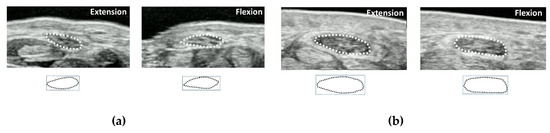

Several ultrasound elastography studies have assessed changes of median nerve mechanical properties in CTS [55,56,57,58,59,60,61,62,63]. In a recent meta-analysis, regardless of the ultrasound elastography mode, median nerves at the wrist level were consistently stiffer in patients with CTS than those in healthy controls [64]. There were several different parameters used to evaluate material property changes of median nerve, i.e., color diagram, strain, strain ratio, shear wave velocity, and shear modulus. There are various cutoff values for each method, due in part, as well, to differences in the measurement principles with different ultrasound systems. For strain imaging, strain of the median nerve is the most generally applied parameter. In some strain elastography-based studies, mean tissue strain in the CTS patients group was significantly lower than in the healthy controls [59,63,65]. Although there were no clear descriptions for the accuracy, the calculated accuracy of the strain measurements was 56.5–70% with the cutoff values of 0.06–0.19. Another approach of using strain elastography is the measurement of color pixels of elastographic images. A higher density of blue pixels (signifying harder nerves) and a lower density of red pixels (signifying softer nerves) were found in the CTS population [55,56]. However, considering the substantial variance in the results in healthy controls, it has been proposed to diagnose CTS based on the wrist-to-forearm ratio of median nerve stiffness, rather than on the basis of the absolute stiffness of the nerve, similar to the cross-sectional area measurements [39]. Since the applied force affects the results of strain measurements, some studies used strain ratio, which is a parameter measuring the ratio of median nerve strain and comparative structures, i.e., fat, tendon, or acoustic coupler [57,65,66,67]. In another study, to standardize the strain measurement, special equipment was developed [58] and subsequently modified with a pressure-monitor ultrasound system [68] (Figure 4). With this equipment, the applied force and displacement of the transducer were more reproducible, and strain with applied force can be evaluated quantitatively.

Figure 4. Pressure-monitor ultrasound system for the quantitative assessment of median nerve strain. (a) Pressure-monitor ultrasound system, (b) elastographic images of CTS patients and normal controls. Upper row shows the image of a normal subject. Lower row shows the image of a CTS patient.